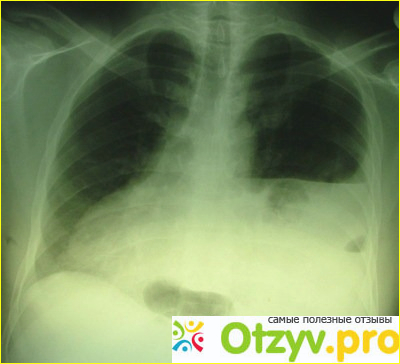

В кабинете меня ждал уже врач-пульмонолог Константин Григорьевич, очень хороший и отзывчивый человек, а главное профессионал в своей области, он меня осмотрел и отправил проходить рентген, где выявилось что у меня острая форма пневмонии - спонтанный гидропневматоракс. Поэтому надо было срочно из меня выкачивать жидкость и воздух, которые скопились в плевральной полости легкого.

Меня отвезли в операционную и сам врач принялся к операции, называется это пункция. Я как только увидел тонкий длинный шприц, а вкалывали в меня обезболивающее я сразу же потерял сознание, я даже ничего не успел почувствовать, потому что дозу он в меня вкачал приличную, проснулся я с банкой в руке. Врач мне все подробно объяснил, как управлять шлангом и что нужно предпринимать, если придется вставать с койки. Постельный режим у меня был целую неделю, но хорошо, что все закончилось успешно. Правда на следующий день меня опять отравили на рентген, опять делали пункцию, только на этот раз со стороны спины и теперь у меня уже было две баночки. Ощущения были конечно же не приятные, когда ты чувствуешь, что с тебя стекает жидкость. Также хочу поблагодарить медсестер, которые ухаживали за мной на протяжении 7 дней. Ко мне каждый день приходили друзья-коллеги, приносили фрукты, а сам врач навещал меня каждый день по несколько раз, помогла медсестре делать уколы, также за мной ухаживал, а также держал меня в курсе новостей. Приходилось сдавать очень много различных анализов и за этот срок, что я пролежал в больнице я три раза делал рентген, меня катали на инвалидной коляске, но слава Богу, что я смог окрепнуть за эти дни. По вечерам нас бесплатно кормили, кстати даже очень вкусно. И вот наконец то я дождался дня выписки, когда врач-пульмонолог мне дал выписной лист, указал какие лекарства мне необходимо принимать для профилактики легких, а также прописал особый режим питания, а также порекомендовал меня бросить курить, ну и отказаться от физических нагрузок, поэтому моя командировка абсолютно в этом плане не удалась.